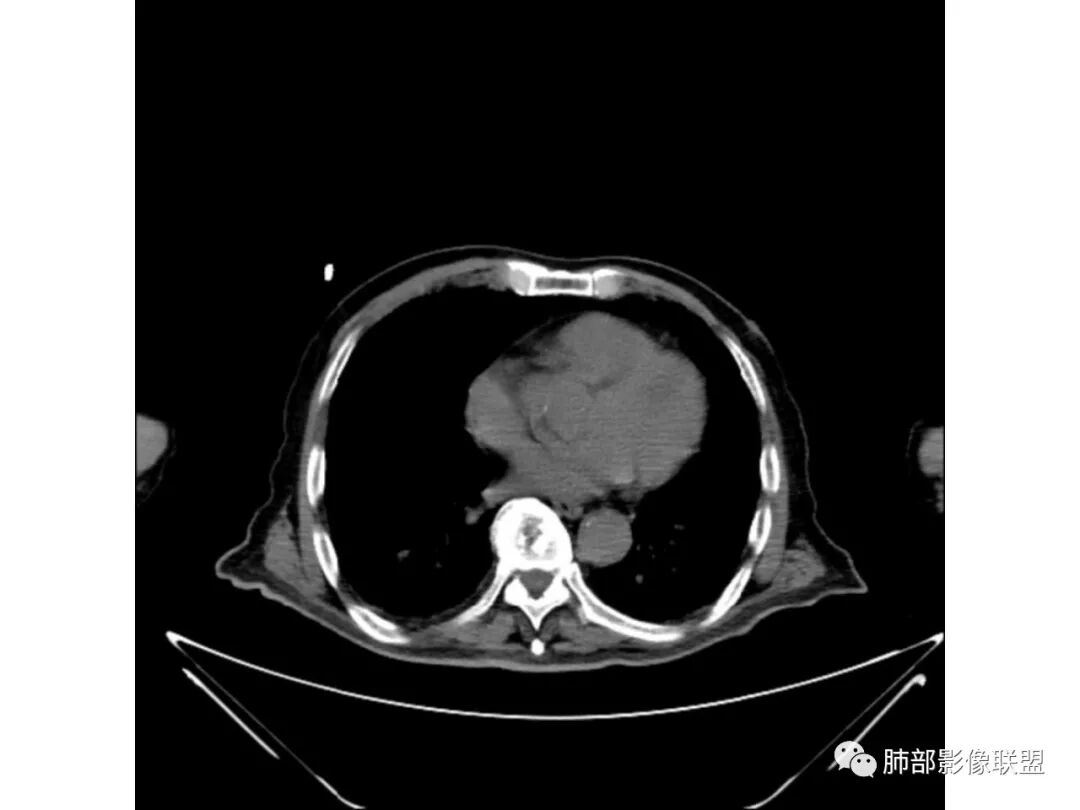

3、增强扫描很重要,增强后,结核的坏死很彻底,很少异常强化,(鳞癌也类同)。而粘液腺癌血管常显影,有时是毛糙的,整体密度偏低,哟其实纵膈窗。

粘液腺癌的很少见纵隔淋巴结肿大,而其他腺癌常见。

如果胸膜下有间隙,不支持肺炎型肺癌